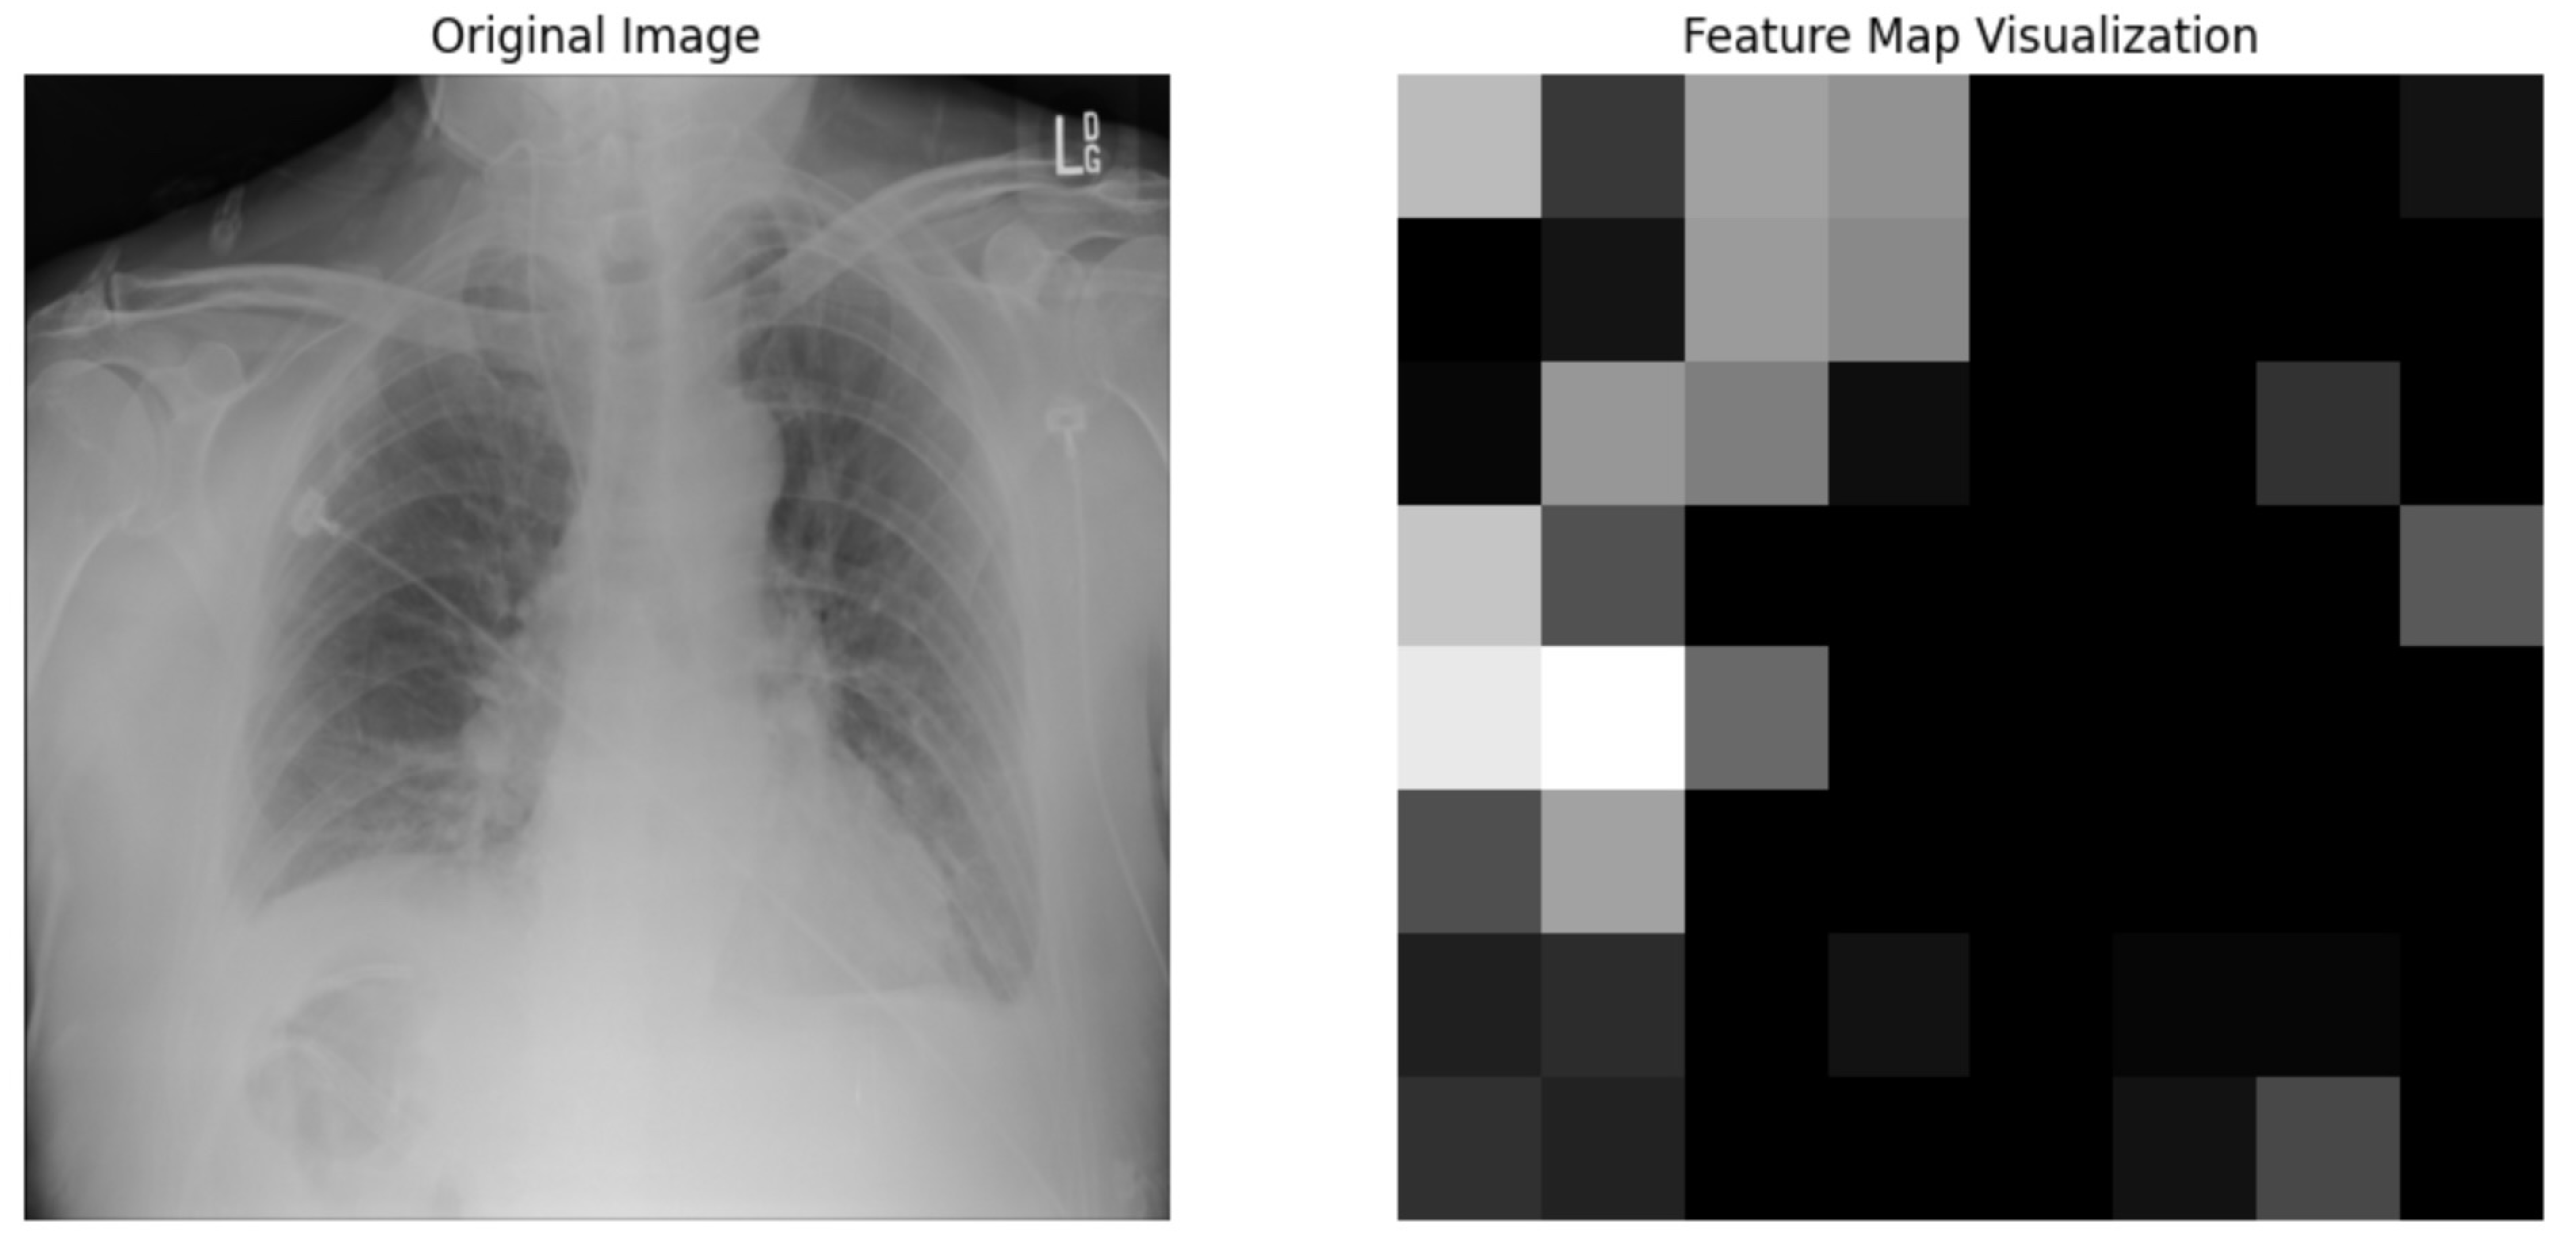

5.4.1. Local Interpretable Model-Agnostic Explanations for Clinical Validation

We applied scientific analysis on a random 7 sample, which was provided by the clinical specialist. The LIME Analysis for Image Data (a), (b), (c), (d), (e), and (f) is in Figure 22, Figure 23, Figure 24, Figure 25, Figure 26 and Figure 27. There are two parts of LIME analysis from the provided chest X-ray images to detect the disease area. Original Image and LIME explanation;

• Original Image: The patient’s thoracic cavity. It displays the typical anatomical structures of the chest, including the lungs, ribs, and heart.

• LIME Explanation: The result of applying LIME to the chest X-ray image. The yellow boundaries indicate the regions of the image that were most influential in the model’s decision-making process when determining whether the image indicated a particular condition. In this context, these regions are the parts of the X-ray that the AI model considered most important for making its diagnostic prediction.

The analysis very useful for clinicians to understand the model’s behavior and ensure that it aligns with medical expertise. The use of LIME helps in making the AI model’s interpretability decisions more transparent and interpretable. It allows medical professionals to verify whether the AI’s focus areas correspond to clinically significant regions. It also enhanced diagnostic capability of understanding which parts of the images in the AI model in refining the model further and ensures that it makes accurate and reliable predictions. This is particularly crucial in medical diagnostics where interpretability and accuracy are paramount.

Figure 22. LIME Analysis for Image Data (a) on original image to LIME explanation.